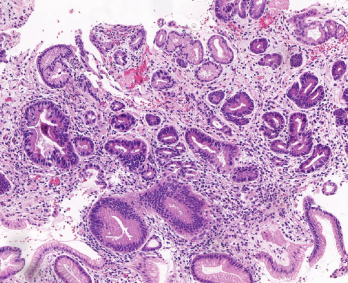

Block interception and precise amplification of gastric biopsy digital images; Tumor segmentation model

and heat map analysis; Feature extraction, negative and positive classification to predict tumor probability with high sensitivity.

1. Identification image: high-quality, direct, accurate, intelligent.

3. WSI reasoning: WSI slide-window reasoning, intelligent zoom in, adenoma identification optimization.